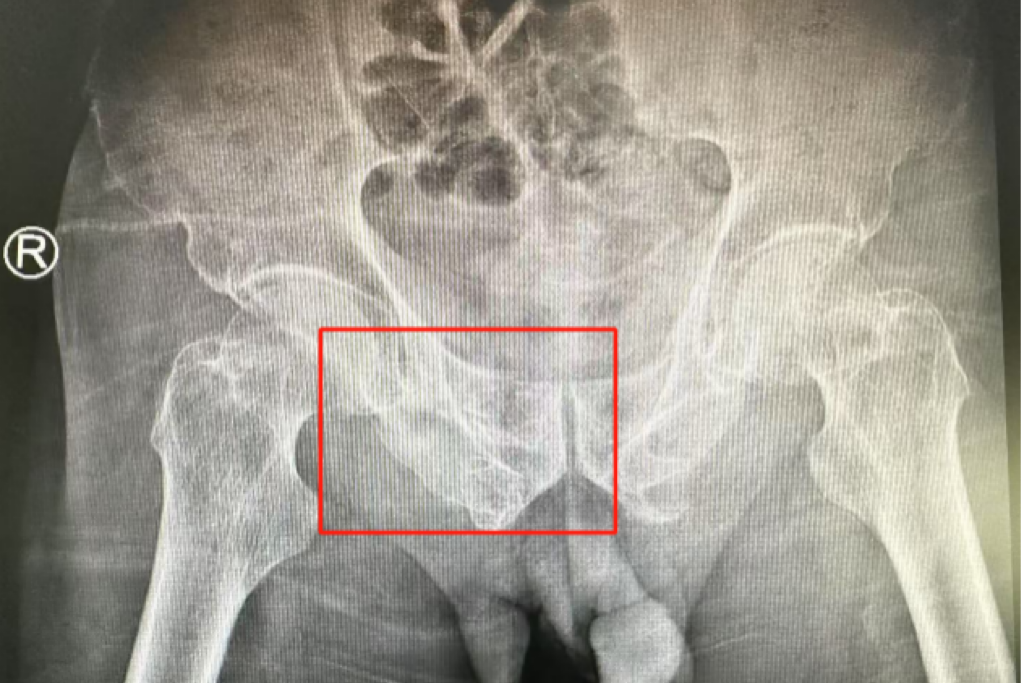

ÊõǰӰÏñѧÏÔʾ£¬£¬£¬£¬£¬£¬£¬»¼ÕßµÄ×ó²à÷¾¹Ç¹ÇÕÛ£¬£¬£¬£¬£¬£¬£¬ÓÒ²à³Ü¹Ç¹ÇÕÛ¡¢÷ĹǹÇÕÛ£¬£¬£¬£¬£¬£¬£¬¹ÇÅè¹ÇÕÛ·ÖÐÍΪCÐÍ£¬£¬£¬£¬£¬£¬£¬ÍíÄê´àÐÔ¹ÇÅè¹ÇÕÛ·ÖÐÍΪIVÐÍ£¬£¬£¬£¬£¬£¬£¬ÊǼ«¶Ë²»ÎȹÌÐ͵Äǰ»·¹ÇÕÛºÍË«²àºó»·¹ÇÕÛ¡£¡£¡£¡£¡£¡£ËùÐÒûÓÐÏÔ×ŵĹÇÅè³öѪ»òÄÚÔàËðÉ˵ÄÌåÏÖ¡£¡£¡£¡£¡£¡£

ÊõºóµÚ¶þÌ죬£¬£¬£¬£¬£¬£¬Ò½ÉúÍŶӸ´²éXƬÏÔʾÂݶ¤Ö²ÈëλÖúÜÊÇÖª×㣬£¬£¬£¬£¬£¬£¬¹ÇÕÛ»ù±¾µÖ´ïÎȹ̸´Î»£¬£¬£¬£¬£¬£¬£¬Í¬Ê±£¬£¬£¬£¬£¬£¬£¬¸´²éµÄȫѪϸ°û¼ÆÊýÖУ¬£¬£¬£¬£¬£¬£¬ÑªºìÂѰ×Ö¸ÊýΪ102g/L¡£¡£¡£¡£¡£¡£ÊõºóµÚÈýÌ죬£¬£¬£¬£¬£¬£¬ÔÚÖÇÄܹǿƲ¡·¿Õչ˻¤Ê¿ÍŶӼ°¿µ¸´Ê¦µÄÖ¸µ¼ºÍÕչ˻¤Ê¿Ï£¬£¬£¬£¬£¬£¬£¬Íõ´óÒ¯¿ÉÒÔ×øÁ¢ÔÚ´²ÉÏ¡£¡£¡£¡£¡£¡£ÊõºóµÚËÄÌ죬£¬£¬£¬£¬£¬£¬Íõ´óÒ¯ÓÀ´Á˳öÔºÈÕ£¬£¬£¬£¬£¬£¬£¬¡°µÃ¿÷ÓÐÁËÕâôÏȽøµÄÒ½ÁÆÊÖÒÕ£¬£¬£¬£¬£¬£¬£¬ÈÃÎÒ»¹ÄÜϵØÐÐ×ߣ¬£¬£¬£¬£¬£¬£¬Ð»Ð»ÄãÃÇ£¡¡±